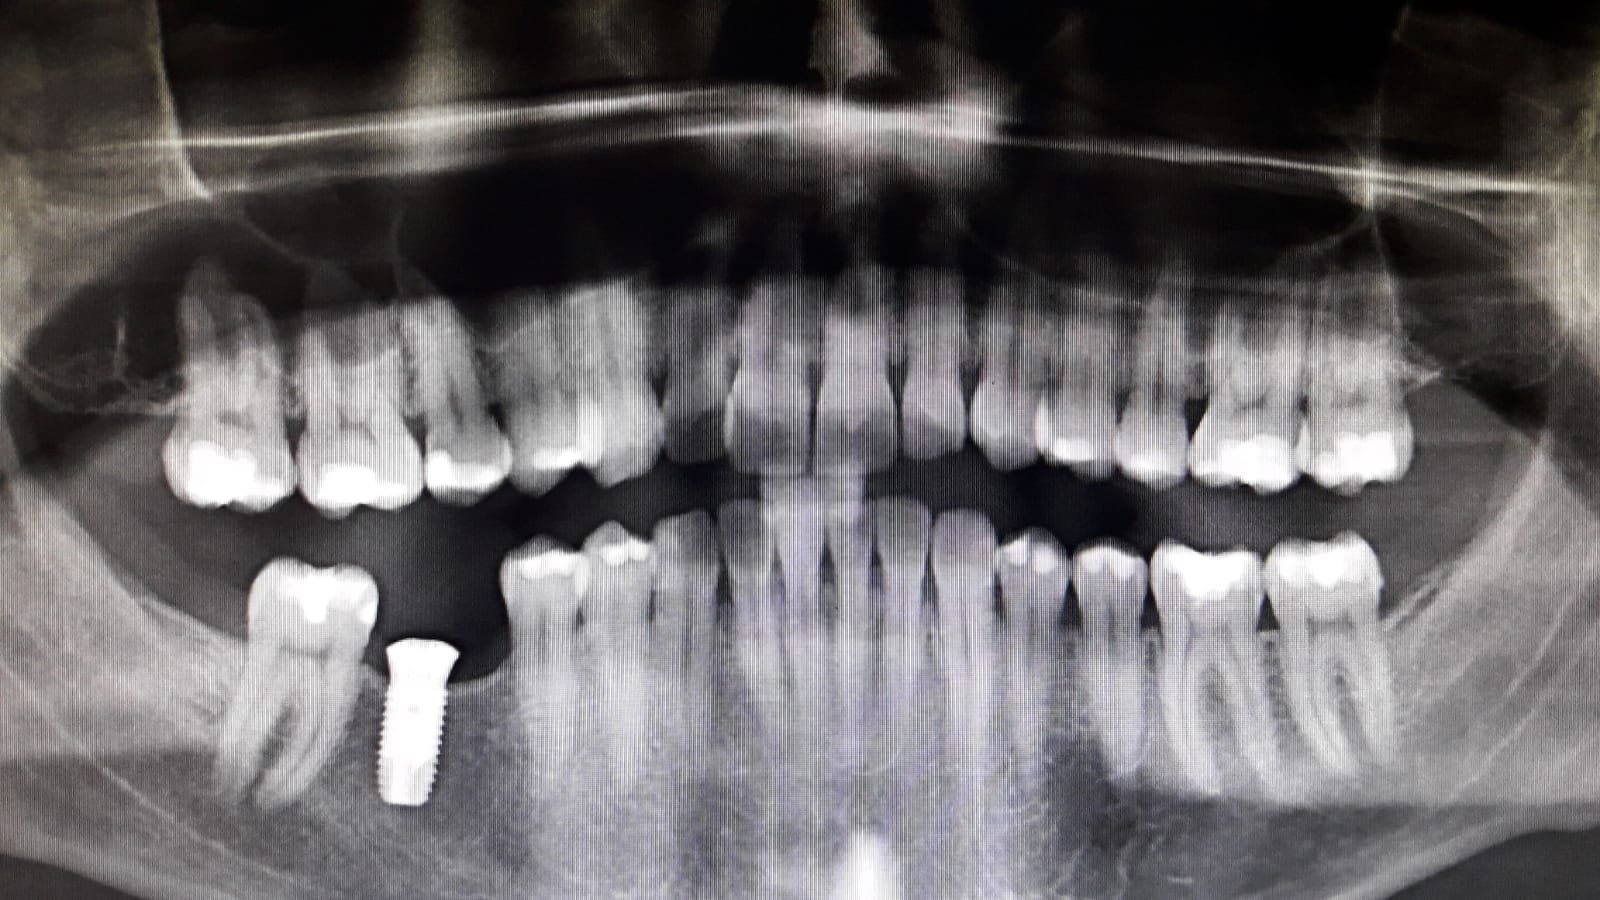

Duda marca y diámetro de implantes en sector anterior.

Paciente de origen colombiano que acude a consulta con 4 implantes colocados en sector anterosuperior en posiciones #12, #11,#21 y #22. Necesitamos conocer la marca y diámetro de los implantes [...]